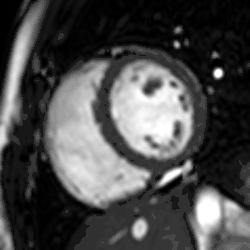

Functional and structural information is acquired using bSSFP cine sequences. These are usually retrospectively-gated and have intrinsically high contrast in cardiac imaging due to the relatively high T2:T1 ratio of blood compared to myocardium. Images are typically planned sequentially to achieve the standard cardiac planes used for assessment. Turbulent flow causes dephasing and signal loss allowing valvular disease to be qualitatively appreciated. The left ventricular short axis cines are acquired from base to apex and are used for quantifying end-diastolic and end-systolic volumes, as well as myocardial mass. Tagging sequences excite a grid pattern that deforms with cardiac contraction allowing strain to be assessed.

Rather, it is typically used in concert with other diagnostic techniques. In general, the clinical reasons for a CMR examination fall into one or more of the following categories: (1) when echocardiography (cardiac ultrasound) cannot provide sufficient diagnostic information, (2) as an alternative to diagnostic cardiac catheterization which involve risks including x-ray radiation exposure, (3) to obtain diagnostic information for which CMR offers unique advantages such as blood flow measurement or identification of cardiac masses, and (4) when clinical assessment and other diagnostic tests are inconsistent. Examples of conditions in which CMR is often used include tetralogy of Fallot, transposition of the great arteries, coarctation of the aorta, single ventricle heart disease, abnormalities of the pulmonary veins, atrial septal defect, connective tissue diseases such as Marfan syndrome, vascular rings, abnormal origins of the coronary arteries, and cardiac tumors.

Enlarged right ventricle with poor function in a patient with repaired tetralogy of Fallot by CMR